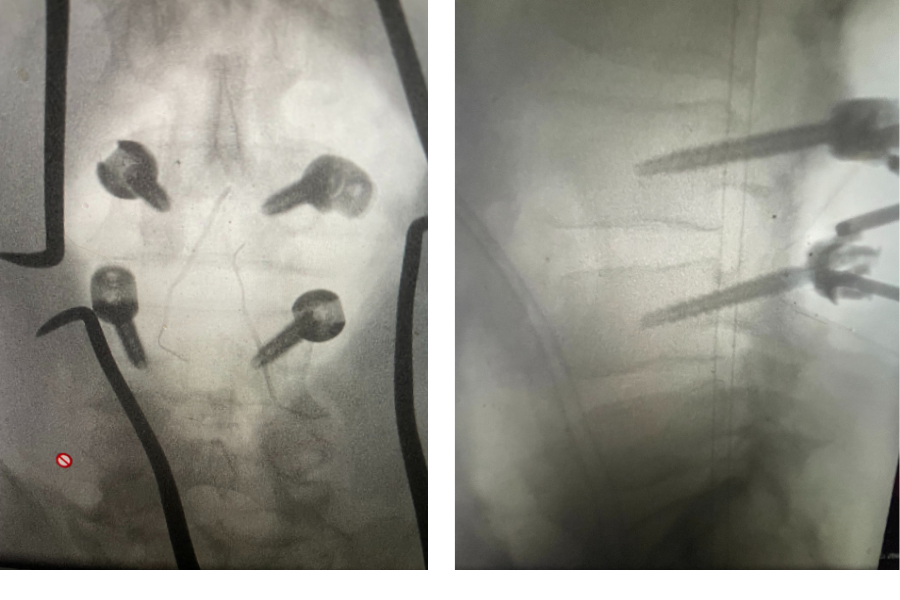

Figure 3. Lateral and AP lumbar intraoperative fluoroscopic images after pedicle screw placement for L3-4 fusion

We elected to perform a decompression from L2-L4. Because the patient had a spondylolisthesis at L3-4

we augmented our decompression with an instrumented fusion at that level, particularly because of the degree of facet joint removal to adequately decompress him (Fig 3). The facet joints were very overgrown and because of that just undercutting the facet would not prove adequate. These facet joints are enlarged because the patient had degeneration of the cartilage and ligaments of the joints, disc space and supporting structures. A common occurrence is for the spinal segment to slip or “listhes” in Greek. In order to compensate for this instability, the body tries to compensate and enlarges what it has available like the joints and the ligaments. In doing so the spine paradoxically hurts itself in creating spinal stenosis. The bone really does not communicate with the nerve sac and therefore the sac is squeezed because of these enlarged structures. The patient did well postoperatively with relief of his left leg pain and ambulated the same day of his surgery.